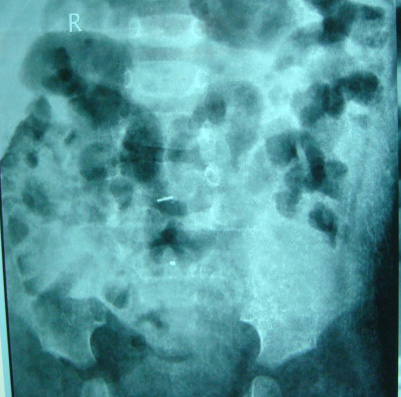

Category: Spinal Dysraphism

Tethered cord syndrome

2. No need of local USG since its operator dependent and even when the lesion is picked up we still do MRI Scan . X-rays would just tell about the spina bifida it does not tell about the intradural patholgy . Ct scan is inferior in detecting the pathology and also exposes the child to radiation So Mri Remains the investigation of choice ideal if I see a child before 1 months we get MRI by 4-5 Months age . we need to reassure the parents no harm happens while waiting.